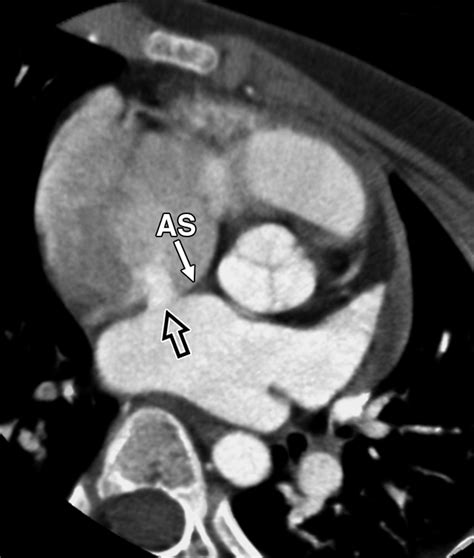

The Amplatzer Septal Occluder is specifically designed to address this by sealing the defect. It is essentially a self-expanding, double-disk device made from a flexible nitinol wire mesh. Once placed, it creates a "sandwich" effect that covers both sides of the hole, allowing the patient's own tissue to grow over the device over time, effectively healing the septal wall.

Not every patient with an ASD is a candidate for the Amplatzer Septal Occluder. The size of the hole, its location within the septum, and the presence of sufficient "rim" tissue (the border of the defect) are all critical factors that determine if the device can be safely anchored. A cardiologist will perform a thorough Transesophageal Echocardiogram (TEE) to map the defect precisely.

Safety is the cornerstone of this medical device. The nitinol mesh used is biocompatible, meaning the body is highly unlikely to reject it. Furthermore, the device is designed to be retrievable before full deployment if the cardiologist determines that the positioning is not optimal, adding an extra layer of clinical safety to the procedure.